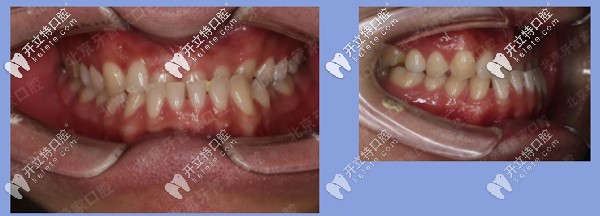

患者地包天牙齒矯正中

矯正時(shí)長(zhǎng):23個(gè)月

矯正結(jié)果:上下前牙反合解除,上唇突度恢復(fù)豐滿,患者非常滿意。

患者地包天矯正后